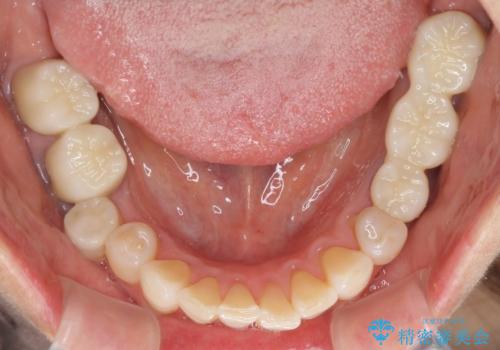

金属を全てセラミックに メタルフリー治療

- 口腔内にある銀歯を全て外したいとのことで来院された患者様です。

土台に含まれている金属も含め、口腔内の金属は全て除去し、抜歯しなければならない歯は抜歯し、オールセラミッククラウンやセラミックインレーにて治療することとしました。

上下奥歯の抜歯を同時期に行わず、下顎の治療を終えてから上顎を抜歯して治療を進めたため、1年ほどの期間を要しました。

口の中を一切気にしなくて良くなり、患者様には大変満足していただきました。